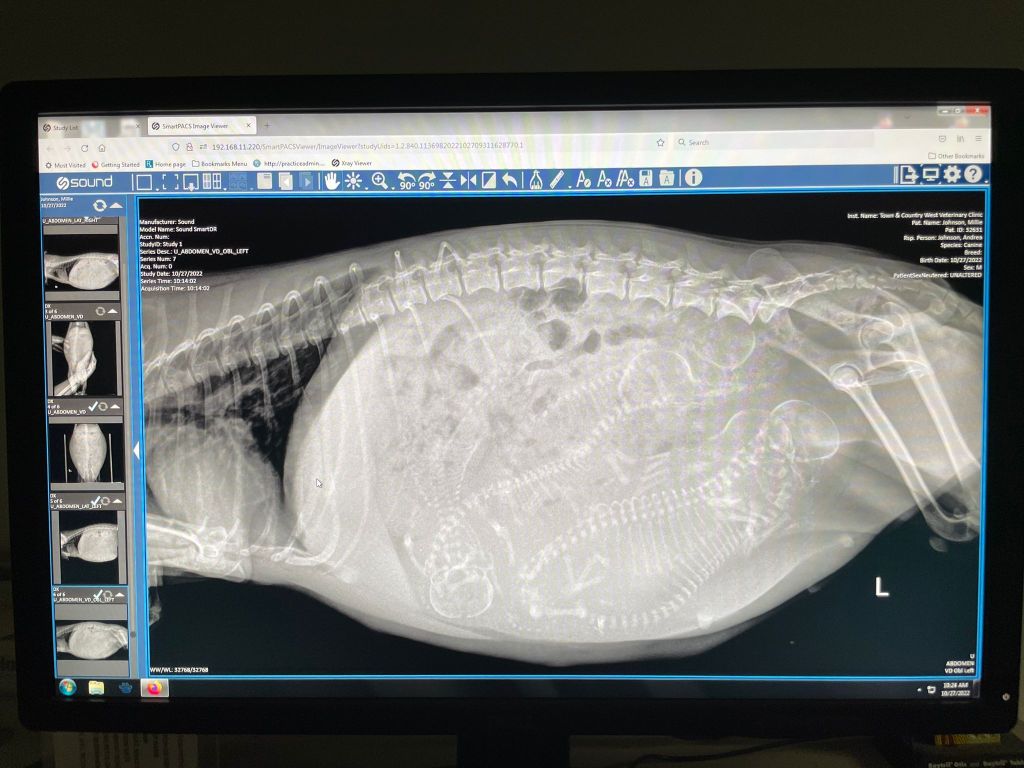

X-RAY VISIT: The x-ray visit took place in the late 50ish day mark, close to whelping. I still don’t know why it’s fine to x-ray dogs when pregnant women are warned ad nauseum not to be x-rate whatsoever at any stage of pregnancy. It’s a good thing we actually did the x-ray – as on this visit, we spotted not three but FIVE puppies! You count them by the spines and skulls you can see. It’s important to know the closest final number you can – just to ensure every puppy makes it out and every corresponding afterbirth (placenta) also makes it out. Quite important – as you can imagine. The other important reason: to gauge the size of the puppies skulls in relation to the pelvic opening of your dam (i.e. mom). Heads that are too big for the space means she is in serious likelihood of needing a c-section – something that’s best prepared for in advance (both from a timing standpoint – extremely critical – and a financial standpoint). Thankfully, it didn’t look like Millie would need one, but we had our emergency vet on standby just in case.

Can you spot all five silky malti pups in the x-ray images below?

Side view x-ray of Millie’s puppies

Front view of Millie’s pups WHELPING AREA